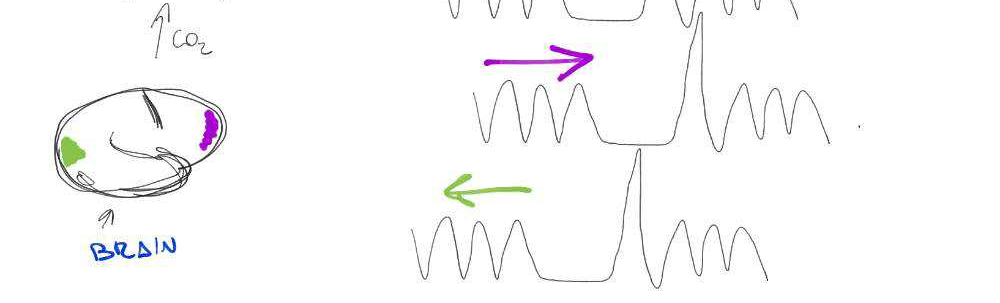

BH-induced CVR: Issues

Two problems:

- There's a measurement delay, and regional variations of the physiological delay

- The BH task presents collinear motion to signal of interest

Motion

CO2

BOLD

BH-induced CVR: Issues

Two problems:

- There's a measurement delay, and regional variations of the physiological delay

- The BH task presents collinear motion to signal of interest

Motion

CO2

BOLD